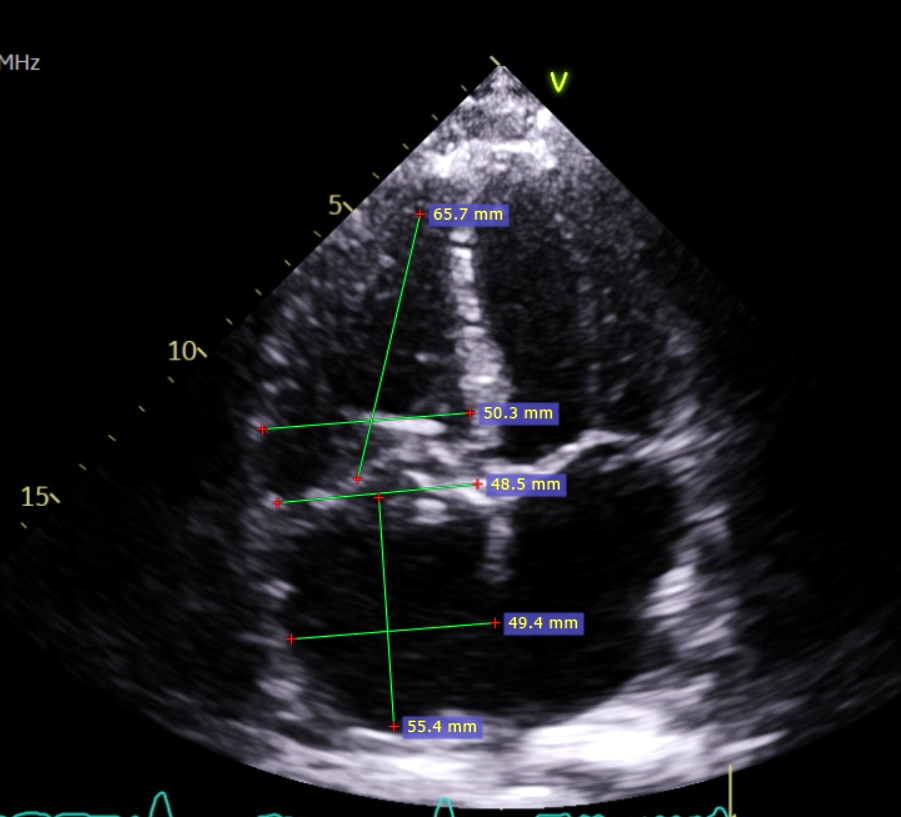

患者手术前后超声对比

术前三尖瓣环前隔径测量值为58.3mm

右心室横径为71.4mm

右心室长径为79.3mm

术后仅四个月三尖瓣环前隔径测量值为48.5mm

右心室横径为50.3mm

右心室长径为65.6mm

从影像来看,右心明显发生重构、缩小